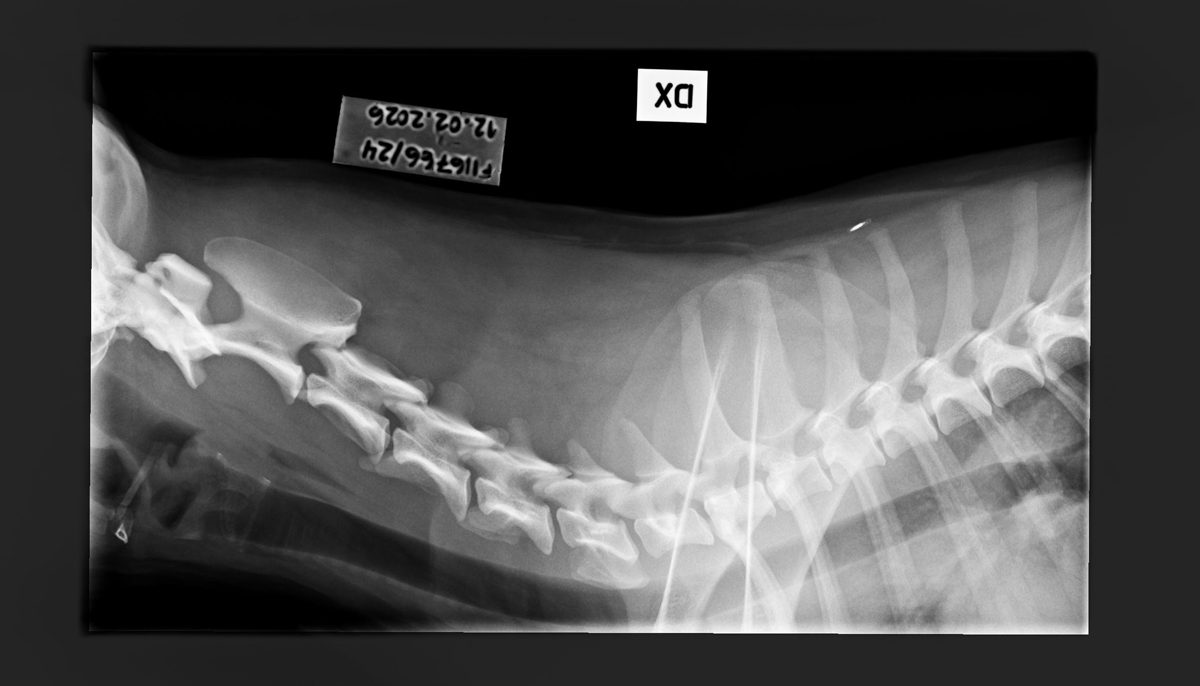

- Free of lumbosacral transitional vertebrae (LTV0)

- Free of spondylosis (SP0)

- Free of vertebral anomalies (VA0)

- Spine x-rays: 1, 2 ja 3